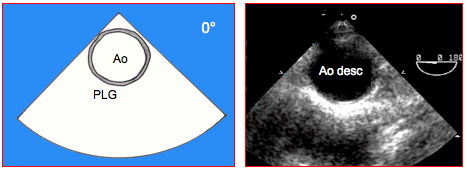

29. Vue court-axe aorte descendante 0° (Vidéo et Figure 25.83)

Figure 25.83 : Vue court axe de l’aorte descendante à 0°. Ao : aorte descendante. PLG : position de la plèvre gauche.